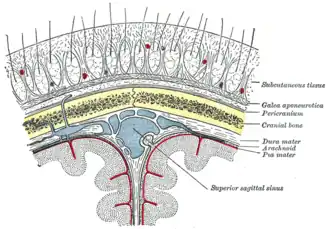

Leptomeningeal collaterals lie within the leptomeninges, the two deep layers of the meninges called the pia mater and the arachnoid mater.[4] Their diameter has been measured at approximately 300 micrometers,[5] but there is variability between individuals in the size, quantity and location of these vessels, and between either hemisphere within the same subject.[6]

The term 'leptomeningeal' derives from the Greek word leptos (λεπτός) meaning thin, in reference to the appearance of the pia mater and arachnoid mater.